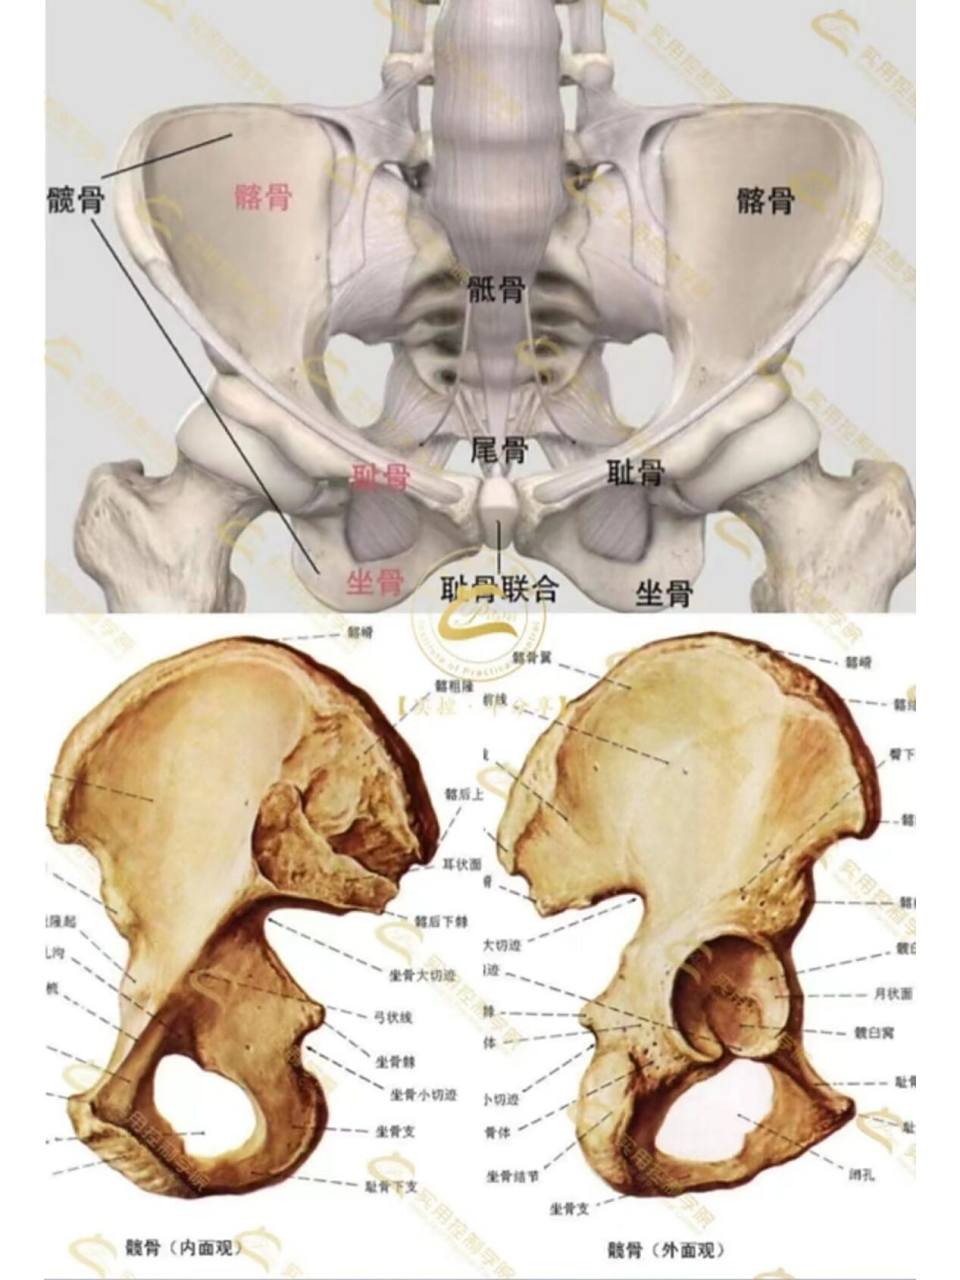

临床必备!

图片尺寸1080x1080

到青春期结束时,三个区域将融合在一起,到25岁时

图片尺寸960x1280